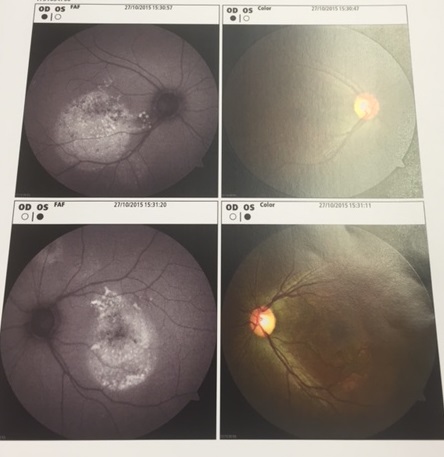

7 Membrana neovascolare sottoretinica (maculopatia) maculare in miope

Paziente di 46 anni riferisce calo visivo nell'occhio di sinistra da circa 2 settimane, l'obiettività oculistica è la seguente:

vod: 10/10 con correzione ottica

vos: 8-9/10 con correzione ottica

too: 15 mmhg

boo: nella norma

fod: sospetto distacco sieroso maculare

fos: nei limiti di norma

Effettuato OCT (vedi allegato): nell'occhio sinistro si evidenzia un distacco sieroso maculare

Effettuata fluorangiografia (vedi allegato): nell'occhio sinistro si evidenzia una membrana neovascolare sottoretinica maculare

Effettuata terapia con iniezioni intravitreali di farmaci anti-VEGF, la neovascolarizzazione è totalmente regredita e la paziente vede con l'occhio sinistro 10/10 con correzione ottica.

Questo caso poteva essere di difficile interpretazione all'inizio per l'assenza di emorragie retiniche maculari che indicassero la presenza di una neovascolarizzazione e per l'evidenza all'OCT di un distacco sieroso che poteva essere anche di altra natura, la fluorangiografia ha permesso di evidenziare l'esatta causa.

Questo ci dimostra come OCT e fluorangiografia siano esami entrambi importanti e con informazioni complementari e spesso è necessario effettuarli entrambi per un corretto studio delle maculopatie.